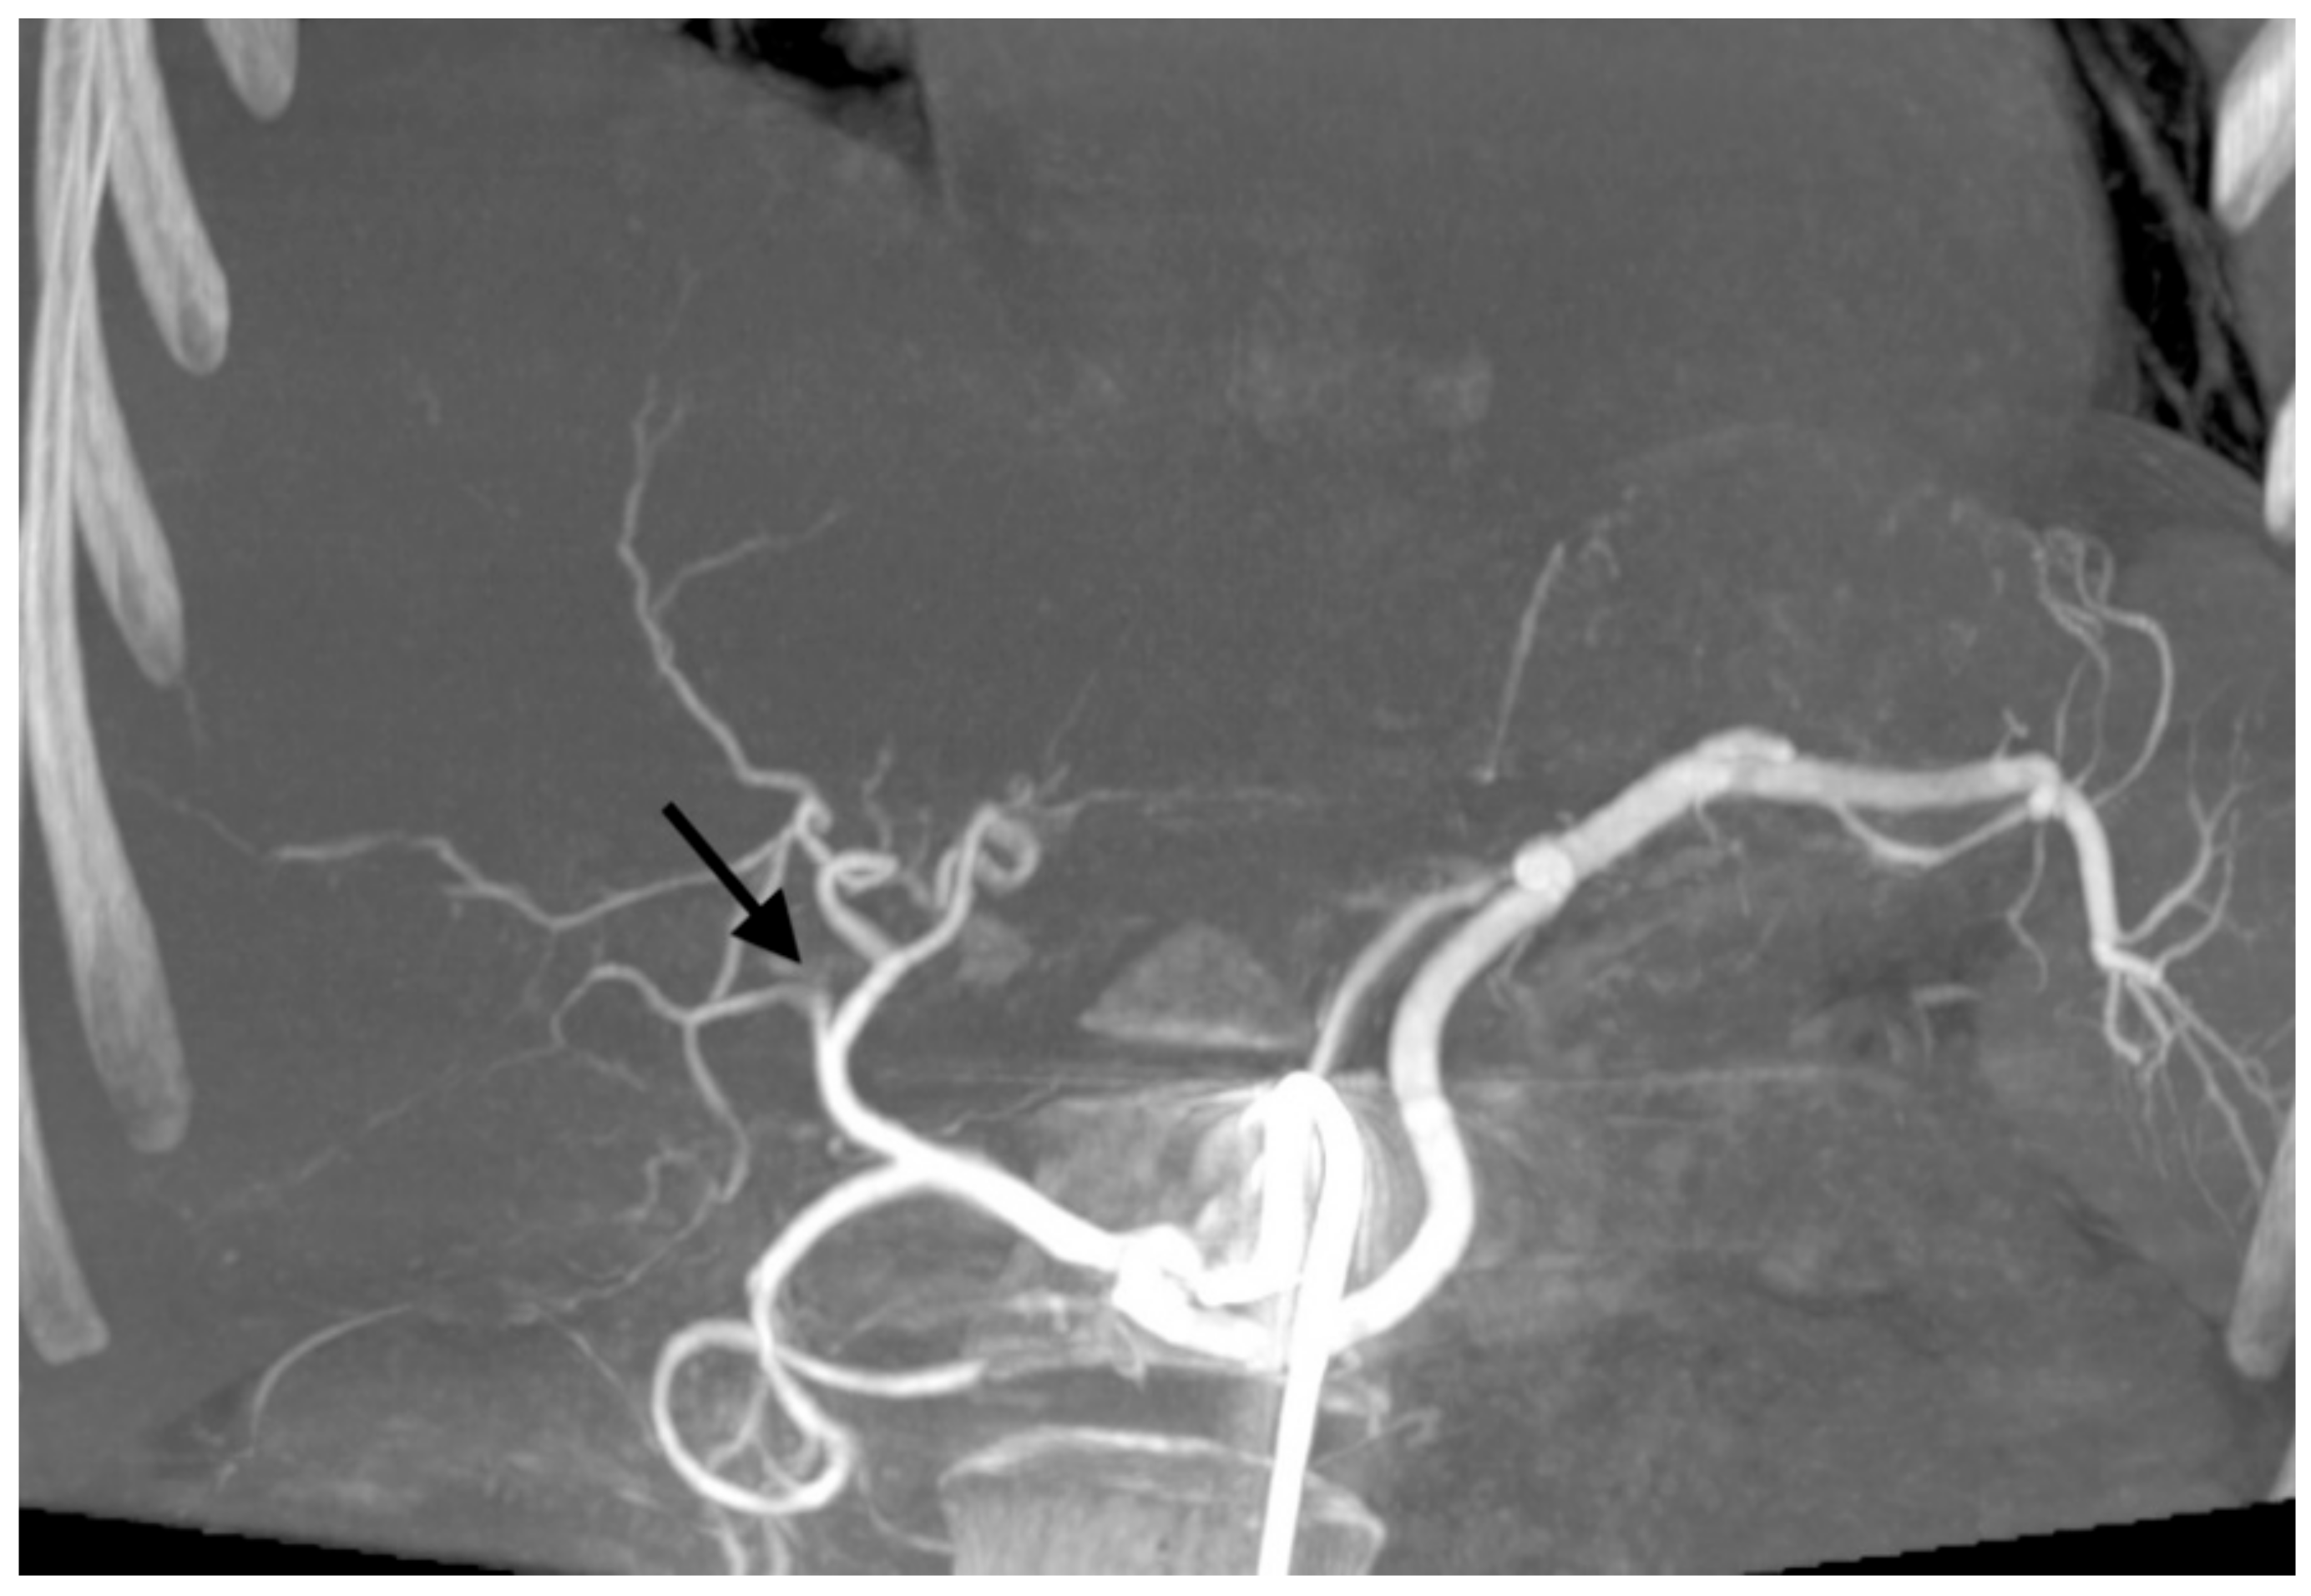

With 192 chemoembolizations, 14 (7.3%) serious complications were found. The most complications were found with the administration of embolizate at the level of the lobar arteries. There was no significant correlation between the branch level of embolization and the presence of complications (chi-squared = 2.9331, df = 2, p-value = 0.2307; Table 5). In two cases, an anaphylactic reaction occurred with moderate hypotension, skin redness, and coughing occurring during the procedure; this resolved after the intervention of the anesthetic team. Two other patients with severe and prolonged pain in the right upper quadrant showed signs of cholecystitis (without bilirubin increase) in ultrasound, which resolved after conservative treatment. In another two patients, features of liver decompensation with ascites were found. One patient experienced a septic episode with liver abscess 2 weeks after the last treatment, which was successfully treated by antibiotic therapy. Follow-up imaging studies showed signs of dilatation of the bile ducts in two patients as a result of damage, (Figure 1). Two patients had occlusion of the right or left branch of the hepatic artery (Figure 2). Three patients, 21 days after surgery, had leukopenia <2000 mm3, requiring the date of the next transcatheter arterial chemoembolization (TACE) session to be shifted by an additional week or two. There were no deaths in the periprocedural period or within 30 days of the procedure.

Figure 2. Cone-beam computed tomography showing occlusion of the right branch of hepatic artery (black arrow) after transarterial chemoembolization with drug-eluting microspheres preloaded with irinotecan.